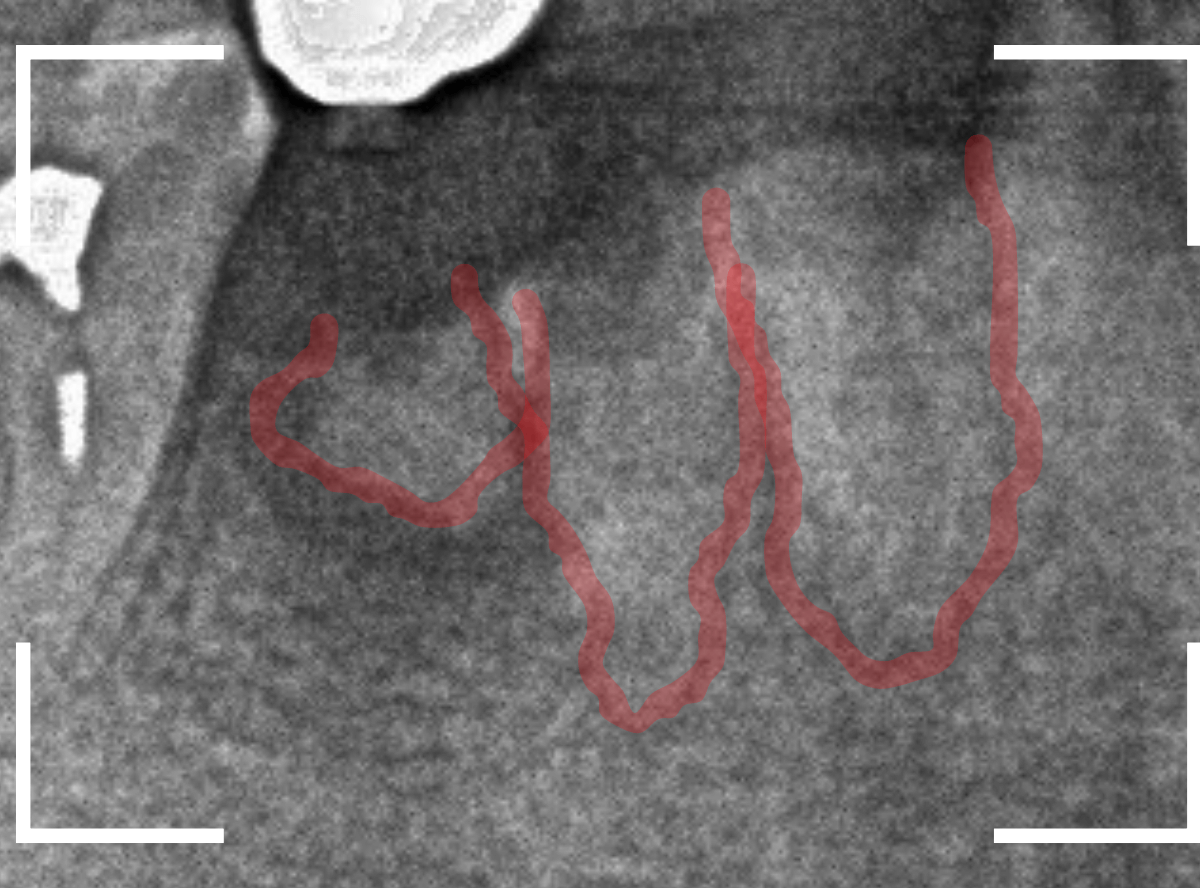

レントゲン写真で確認します。

青い線が歯の形と神経です。

赤い線が、虫歯です。

初見でも想像がつきましたが、かなり虫歯がひどく、治療して再び噛む事が出来るようにするのが不可能で、抜歯をする事になりました。

患者さんも、自覚があったようで、すぐに同意いただきました。